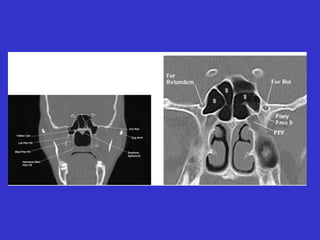

Este documento describe las diferentes proyecciones radiográficas utilizadas para examinar los senos paranasales, incluyendo las proyecciones básicas de Caldwell, Waters lateral y las proyecciones especiales como Hirtz y Waters mentonasal. También describe las diferentes estructuras anatómicas que componen el complejo ostiomeatal anterior y posterior de los senos paranasales.